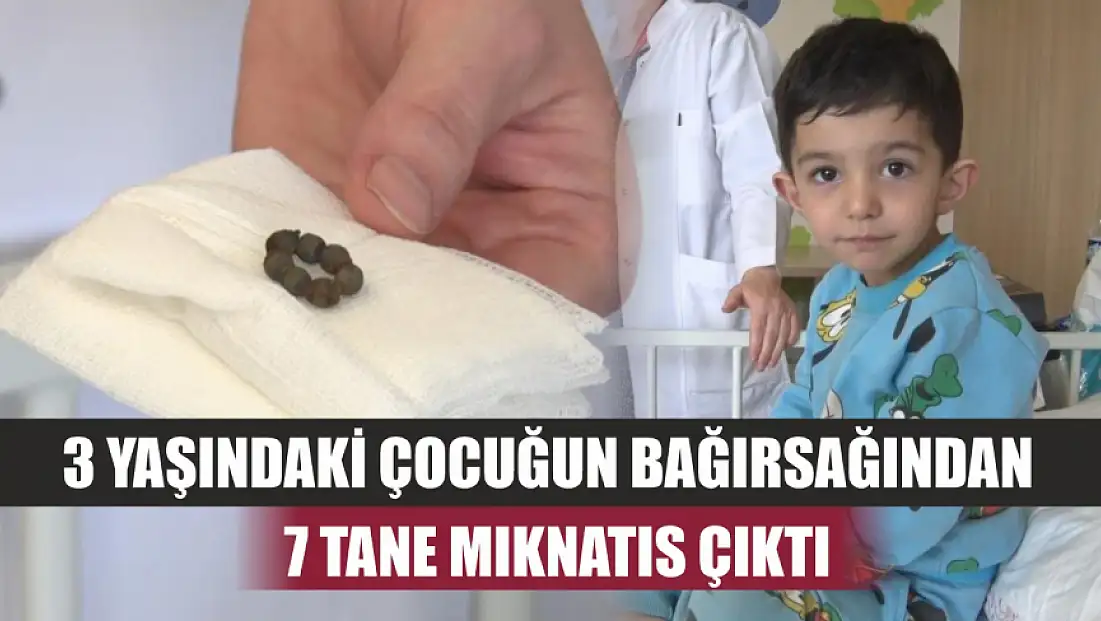

Çocuklarda bu belirtilere dikkat